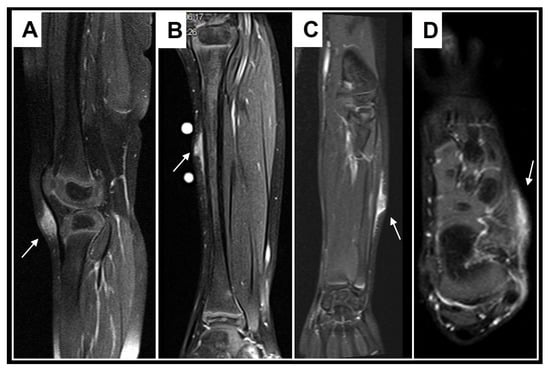

Figure 10.

These images show representative MRI slices through SGA (indicated by white arrows) at the knee (A); lower leg (B); forearm (C); and foot (D) in four different cases. Note that all SGA lesions show the typical epifascial extension with gradual rise of the lesion towards the more superficial tissues, which we have named the “epifascial cap” sign.

A retrospective review of all MR images showed that all MRIs of patients with low-flow SVMs showed multicystic and/or tubular lesion appearance, whereas MRIs of patients with SGA never showed any cyst-shaped structures. An SGA presents as a raised-rounded homogenous mass that projects over the surface of the muscle’s fascia without invading the underlying tissue (Figure 9). These lesions have a typical broad circular base laying on the fascia and a raised, continuous, irregular curved surface that extends from the deep fascia towards the more superficial tissues. One can easily describe the shape of an SGA as an island rising from the ocean. We recently named this characteristic shape “the Epifascial Cap,” the hallmark shape of an SGA (Figure 10) []. The enhancement of contrast material seen in these lesions during the MRI is homogenous and should not be mistaken for a low-flow SVM (Figure 11).

An SGA is isointense relative to the muscles on T1-weighted images and hyperintense relative to the muscles on T2-weighted images. In addition, SGA is homogeneous in both T1- and T2-weighted MRI sequences and shows variable enhancement after contrast material injection. If the epifascial cap shape is visualized on MRI evaluation, consider SGA as the final working diagnosis, and request a clinical follow-up of the lump in 3 months with a repeat ultrasound evaluation to assess the size of the lesion.